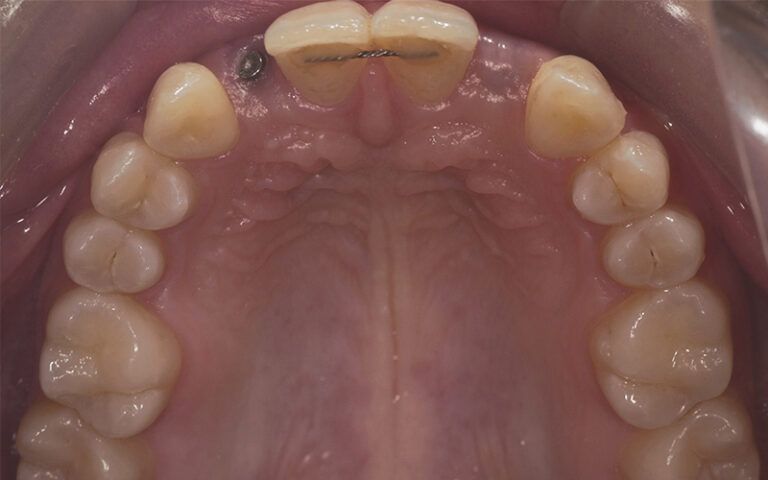

Images of the osseointegration period of the implants and healing of the tissues Images of the osseointegration period of the implants and healing of the tissues Images of the osseointegration period of the implants and healing of the tissues Images of the osseointegration period of the implants and healing of the tissues

After three months of osseointegration, the second surgery performed on both implants and the digital impressions were taken with the TRIOS (3Shape) intraoral scanner.